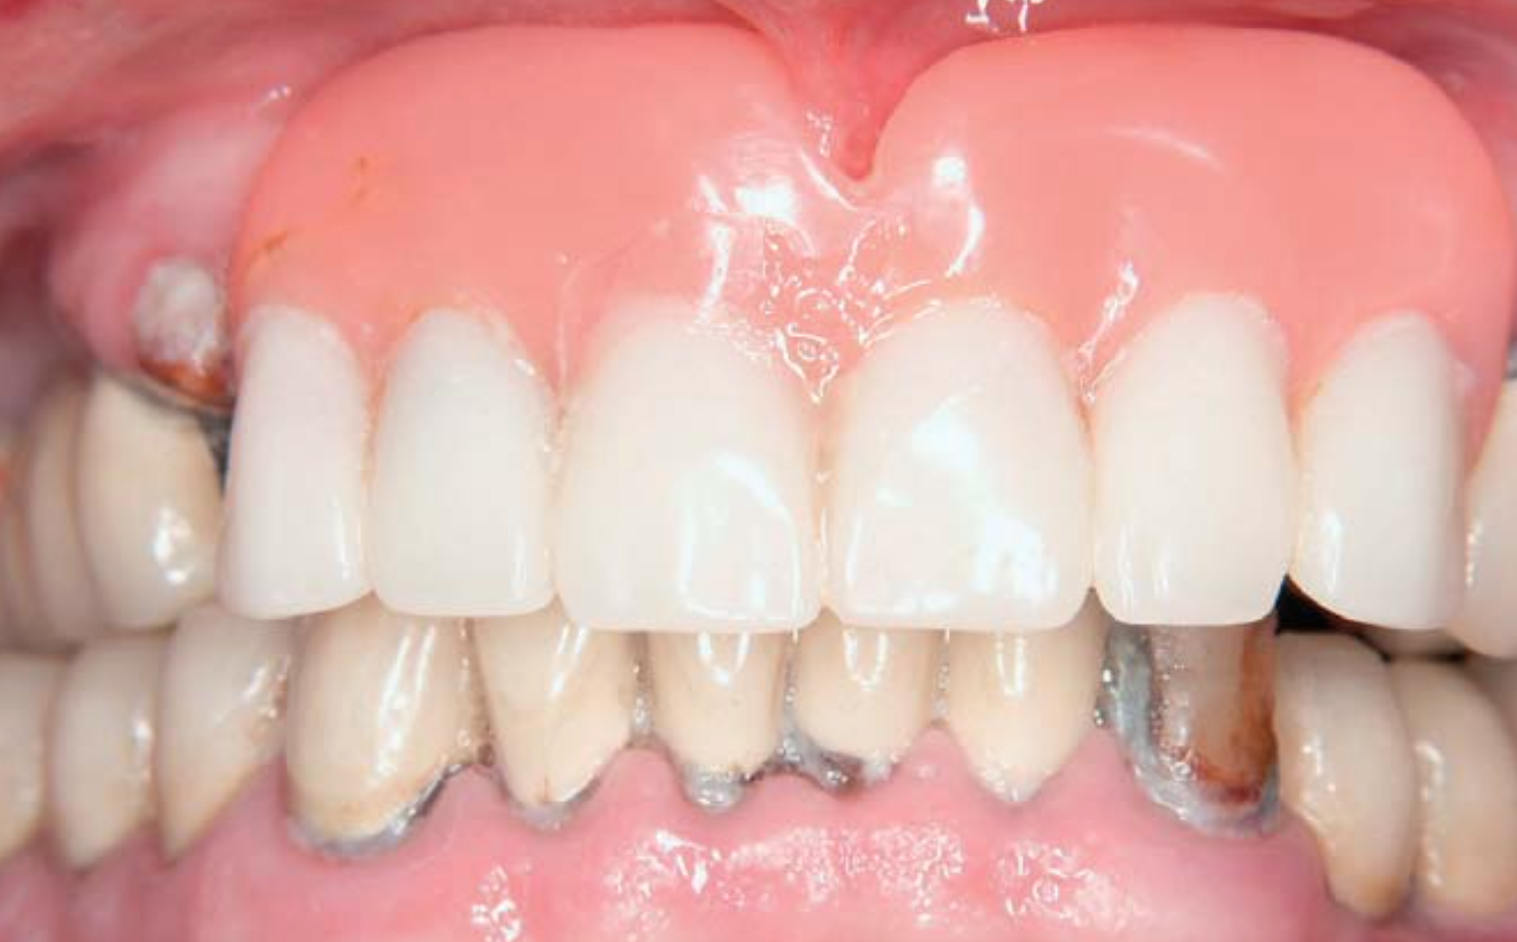

Der vorliegende Artikel gibt einen aktuellen Überblick über die verfügbare Datenlage zur Mundgesundheit pflegebedürftiger Senioren und entsprechende Konzepte zur Verbesserung der Mundgesundheit. Die Mundhygiene und damit längerfristig auch die Mundgesundheit von Senioren in Pflegeheimen – insbesondere bei Demenz – ist oftmals eingeschränkt. Dies hat einerseits negativen Einfluss auf die Kaufunktion und damit die Ernährung, andererseits bestehen Wechselwirkungen mit Allgemeinerkrankungen (Pneumonie, kardiovaskuläre Erkrankungen, Diabetes). Da die Inanspruchnahme zahnmedizinischer Leistungen vieler pflegebedürftiger Senioren aufgrund von Immobilität, finanzieller Restriktionen oder Bedeutungsverlust der Mundgesundheit mit zunehmendem Alter abnimmt, gewinnen zahnärztliche Haus- und Heimbesuche an Relevanz. Zudem wurden in letzter Zeit einige praxistaugliche Interventionskonzepte zur Verbesserung der Mundgesundheit dieser Gesellschaftsgruppe hinsichtlich ihrer Wirksamkeit überprüft. Hauptsächlich wurde der Effekt von professionellen Zahnreinigungen oder Schulungen von Pflegemitarbeitern auf die Mundgesundheit der pflegebedürftigen Senioren untersucht. Da in dieser Population herausnehmbarer Zahnersatz häufig ist, wurde zudem versucht, die Prothesenhygiene mittels manueller, chemischer und/oder physikalischer Reinigungsverfahren zu verbessern. Insgesamt wurden professionelle Zahnreinigungen eher bei leichter pflegebedürftigen Senioren und in Kombination mit individueller Motivierung und Instruktion zur Mundpflege durchgeführt. Auf Grundlage der vorliegenden Ergebnisse kann kurz- bis mittelfristig mit einer dentalen Plaquereduktion von bis zu 60 % gerechnet werden. Auch Personalschulungen können als effektiv bewertet werden. Hier liegt das Verbesserungspotenzial der meist stärker pflegebedürftigen Senioren auch längerfristig gesehen zwischen 15 und 25 %. Zudem scheinen Personalschulungen auch einen positiven Effekt auf die Prothesenhygiene zu haben. Die Implementierung von Ultraschallbädern in Pflegeheimen scheint allerdings die effektivste Maßnahme zur Verbesserung der Prothesenhygiene zu sein. Viele der Interventionskonzepte sind einfach und kostengünstig realisierbar und sollten daher flächendeckend in den Pflegealltag integriert werden. Allerdings sind weitere Studien mit längeren Beobachtungszeiträumen und größeren Stichprobenumfängen als bei bisher verfügbaren Studien erforderlich, um die Erkenntnisse auf einem noch höheren wissenschaftlichen Niveau abzusichern.

This article gives an update on data of oral health in care dependent older people and presents respective options to improve their oral health conditions. Oral hygiene and therefore, long-term oral health of older people in nursing homes – primarily of those suffering from dementia – frequently deteriorates. This impacts chewing function (nutrition) but also intercorrelates with systemic diseases (pneumonia, cardiovascular diseases, diabetes). Dental (nursing) home visits become relevant with aging due to a decrease in utilization of dental services because of older people’s immobility, oral neglect or financial restrictions. Nowadays, practicable interventions for improvement of oral health in this community have been tested for effectiveness. The main interventions are professional tooth cleaning or dental education of nursing staff. Moreover, attempts to improve denture hygiene (manual, chemical, physical denture cleaning) have been evaluated since older people in nursing homes frequently wear removable dentures. As professional tooth cleaning combined with individual instruction and motivation for oral care was rather tested in more or less independent older people, education for nursing staff was used in more dependent communities. Professional tooth cleaning results in reductions of dental plaque accumulation short- and midterm up to 60%. The improvements of dental hygiene due to implementation of education for nursing staff range between 15 and 25%. Besides positive effects of these education programs on denture hygiene, especially the implementation of ultrasound baths seems to be an adequate measure in improving denture hygiene. Many of these concepts can be easily and cost-effectively implemented in daily care routine. One should keep in mind that further research with longer observation periods and larger samples is desirable to confirm the results on a high level of evidence.